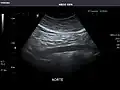

Kidneys: Right and left kidneys measure 11.5 cm and 12 cm in length respectively. No hydronephrosis. Small left lower pole kidney cyst.

Right kidney